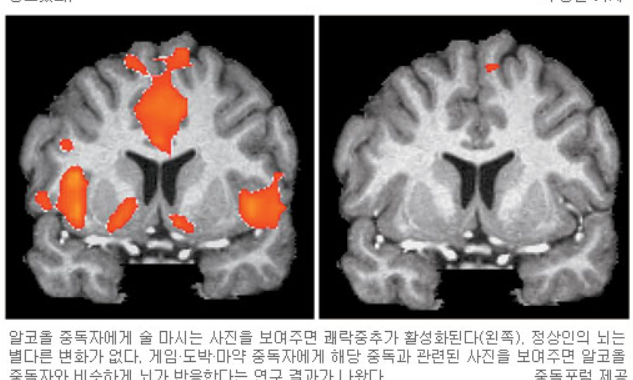

전문가들에 따르면, 뇌에는 보상회로가 있고 이곳이 자극을 받으면 대상은 쾌락을 느낀다. 투기를 통해 돈을 번 사람은 짜릿한 쾌감이 뇌에 선명히 입력된다. 문제는 쾌감을 관장하는 뇌의 쾌락 중추는 같은 수준 혹은 그 이상의 쾌감을 지속적으로 갈망하고, 대상은 쾌락을 줬던 행동을 (이를테면 마약, 술, 도박, 섹스, 게임, 쇼핑 그리고 가상화폐 매매 등) 반복할 유혹에 빠지기 무척 쉽다는 것이다. 이러한 행동이 반복되고 끊기 어렵다면, 이것이 바로 중독이다. 무서운 점은 이러한 중독의 과정은 무의식적으로 이뤄지기 때문에 중독의 대상이 자신이 중독되고 있는지조차 인지하지 못한다는 점.

중독 뇌.png 중독자의 뇌에서 활성화 된 쾌락중추

중독 뇌.png